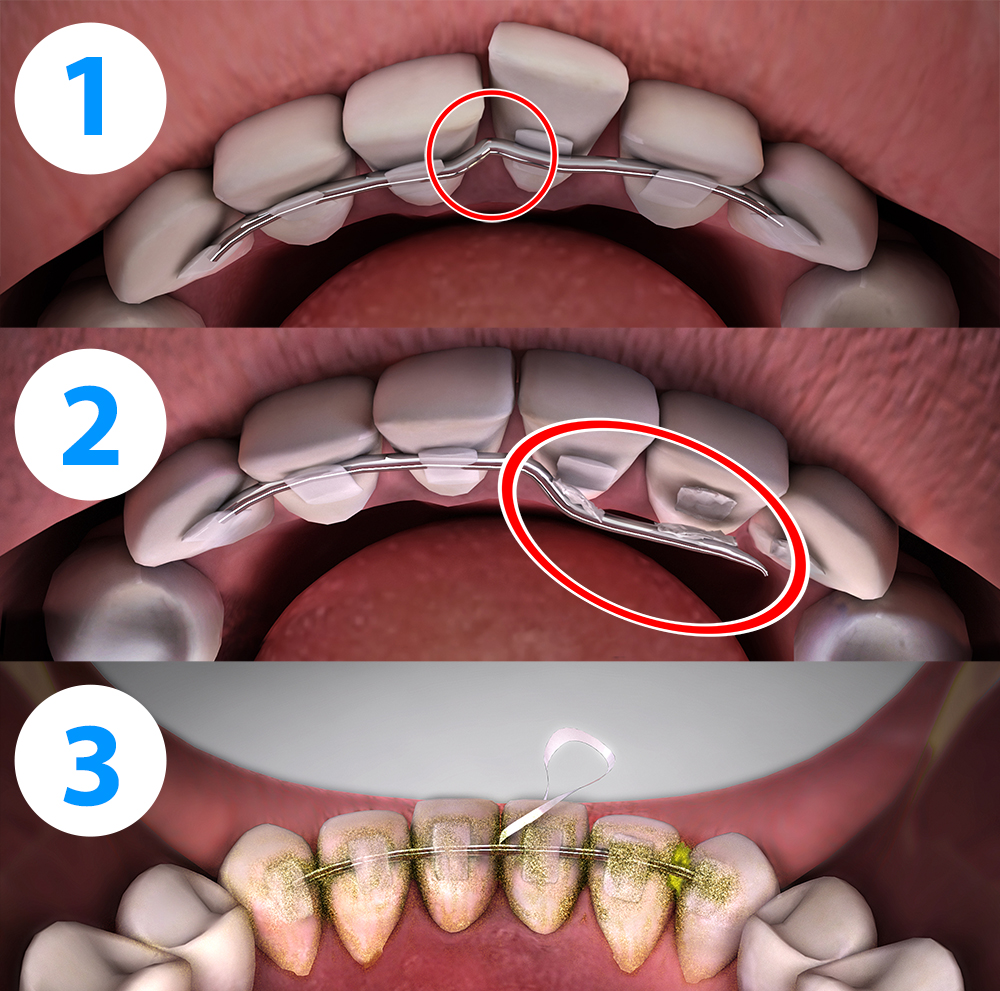

Структура зубов изнутри: фотографии и объяснения

Раздел: Фотомир